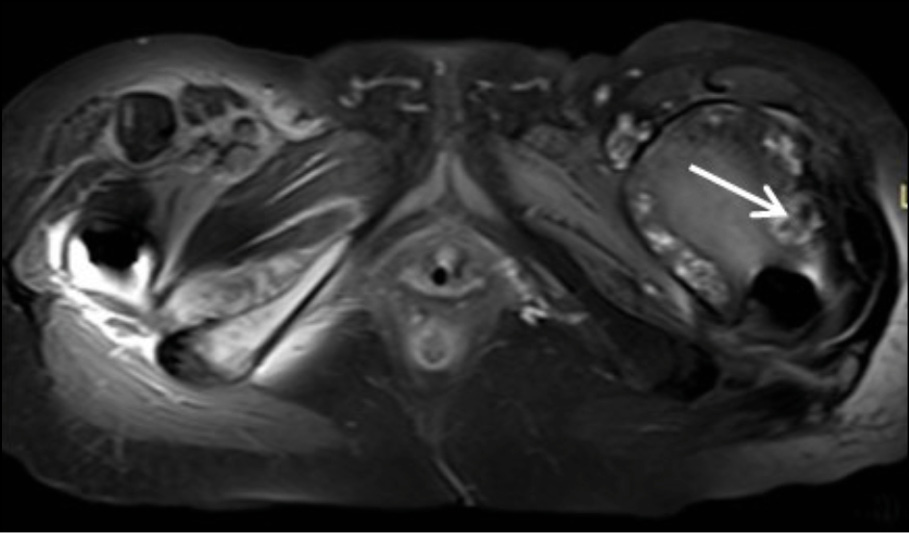

The chest X-ray was normal, with no hilar lymphadenopathy observed. Standard hip radiography was satisfactory and did not show any obvious alterations around the implant (Figure 1). The patient’s white blood cell count was 17.2×109/L with a neutrophilia (14.2 × 109/l), C-reactive protein (CRP) of 20mg/l (<0.5 mg/l), thrombocytopenia, elevated fibrinogen (478 mg/dl), and elevated high-sensitive troponin (1893 ng/dl), which was attributed to Type II ischemia, which further refers to a form of ischemia associated conditions that cause an imbalance between myocardial oxygen supply and demand. The patient was initially administered piperacillin - tazobactam and daptomycin intravenously (i.v). Due to persistent pain which extended above the knee the next days, the patient underwent Magnetic Resonance Imaging (MRI) (Figure 2a-e). MRI showed large encapsulated multilobular fluid collection with internal septa adjacent to the endoprosthesis of the left hip joint (Figure 2a-2b). This collection extended anteriorly beneath the deep fascia, causing displacement of the quadriceps muscle and protruding into the iliopsoas pouch. Its maximum outer diameter measured 12 cm.

Figure 2a - Axial STIR image at the level of femoral neck. Large encapsulated multilobular fluid collection with internal septa is observed adjacent to the endoprosthesis of the left hip joint (white arrows).

Figure 2b - Coronal STIR image at the level of pubic bone. Large encapsulated multilobular fluid collection with internal septa is depicted adjacent to the endoprosthesis of the left hip joint (white arrows).